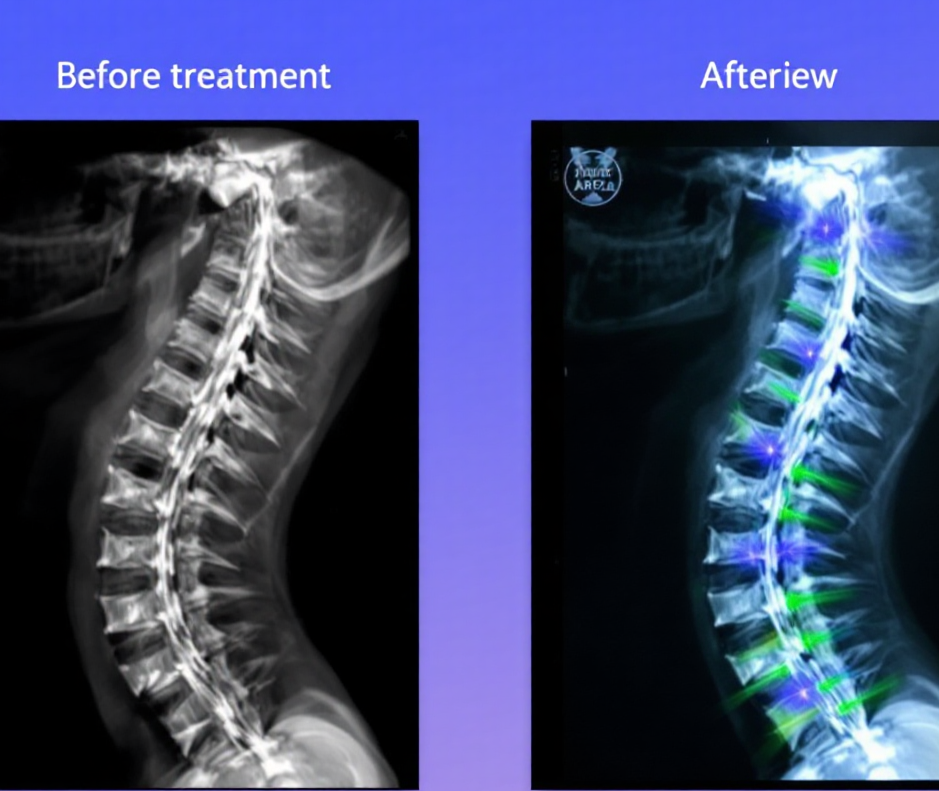

MRI 등 영상자료와의 병행 해석이 필요합니다.

• 허리디스크 탈출 방향과 정도 분석

• MRI, 근전도 등과 함께 종합 해석 필요